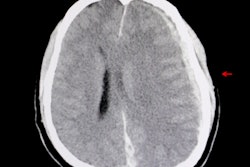

Recently, Dutch Finance Minister Wopke Hoekstra made a somewhat provocative and little nuanced remark while describing expected changes on the labor market during the general financial outlook. He declared that together with cashiers, radiologists will be "mostly unnecessary, since machines have become better at reading medical images than a human who has spent 10 years studying for this task," and gave this as an example of progress.

I agree with Hoekstra that certain tasks can be automated, such as detection and classification of pulmonary nodules or quantification of disease. In fact, it would be great if machines could take care of part of our constantly increasing workload, and this is indeed realistic.

While the performance of computers has dramatically improved, so far automated tasks concern very well defined, specific questions that represent only part of the complete clinical picture. Problem-solving using contextual information is a task that is very hard for computers but comes naturally to humans. The latter is what takes advantage of human interaction, and it requires medical experience and is a growing part of modern, innovative medicine.